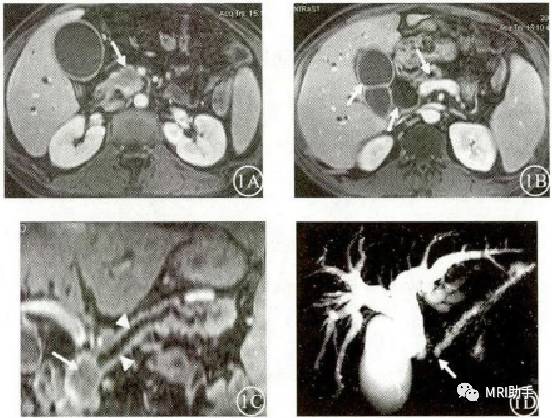

图1A:胰头钩突肿块(白箭),边缘轻度强化,境界清楚。1B:肿块近端胆胰管、胆囊扩张(白箭)。1C:胰管均匀增粗(白箭头),在胰头钩突处(白箭)突然截断,与MRCP(1D)显示的胰管扩张和截断(白箭)征象一致

胰头癌MRCP:胆总管扩张,梗阻端呈锥形,主胰管明显扩张并在肿块处中断